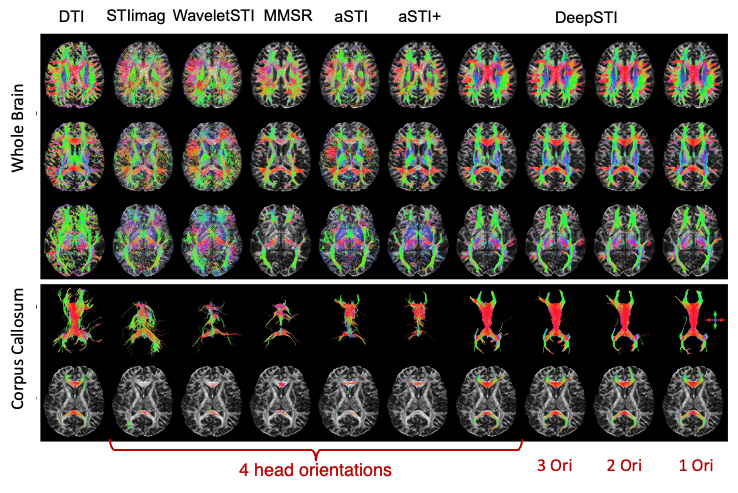

In Vivo Tensor Reconstruction using DeepSTI

DTI

STIimag

[Li et al.]

MMSR

[Li and Van Zijl]

aSTI+

[Shi et al.]

DeepSTI

(ours)

[1] Li et al, NMRB 2017; [2] Li and van Zijl, MRM, 2014;

[3] Cao et al., MRM, 2021; [4] Shi et al., IEEE JBHI, 2022

[5] Fang et al. Medical Image Analysis, 2023

In Vivo Fiber Tractography using DeepSTI